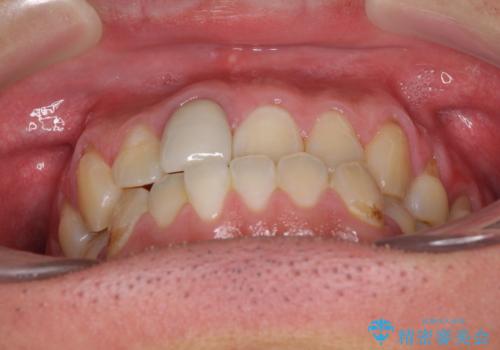

前歯のデコボコとクロスバイトをインビザライン矯正で改善

- 前歯のデコボコと上下のクロスバイトを気にして来院された患者様です。

インビザラインを用い、IPR(歯と歯の間を削る)と歯列全体を拡大させることで、歯並びを整えていくこととしました。

上の前歯が下の前歯を乗り越える際、奥歯がほとんど咬めない時期があり、乗り越えた後も、インビザライン特有の奥歯の咬みにくさが続きました。

咬み合わせ改善のために治療期間を要しましたが、最終的に奥歯はしっかりと咬めるようになりました